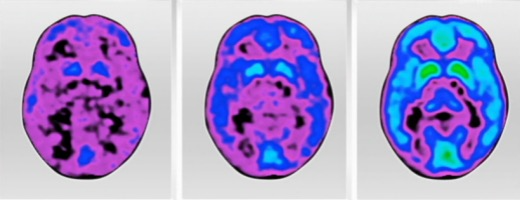

我们提到的第一个阶段,也即是Aβ的堆积,在40岁的时候就已经开始。这是一位遗传型病人从40到80岁的头部扫描,我们在40岁的扫描中已经能清楚地看到Aβ蛋白的堆积(蓝色区域),

而病人在70岁左右表现出症状时,Aβ的堆积几乎已经遍布全脑,在对记忆至关重要的海马体(hippocampus)附近更是已经非常集中,这基本上意味着在症状出现时,神经元早已经开始大面积地死亡。